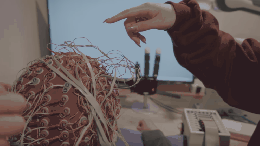

- СейчасБионика. Живые радары